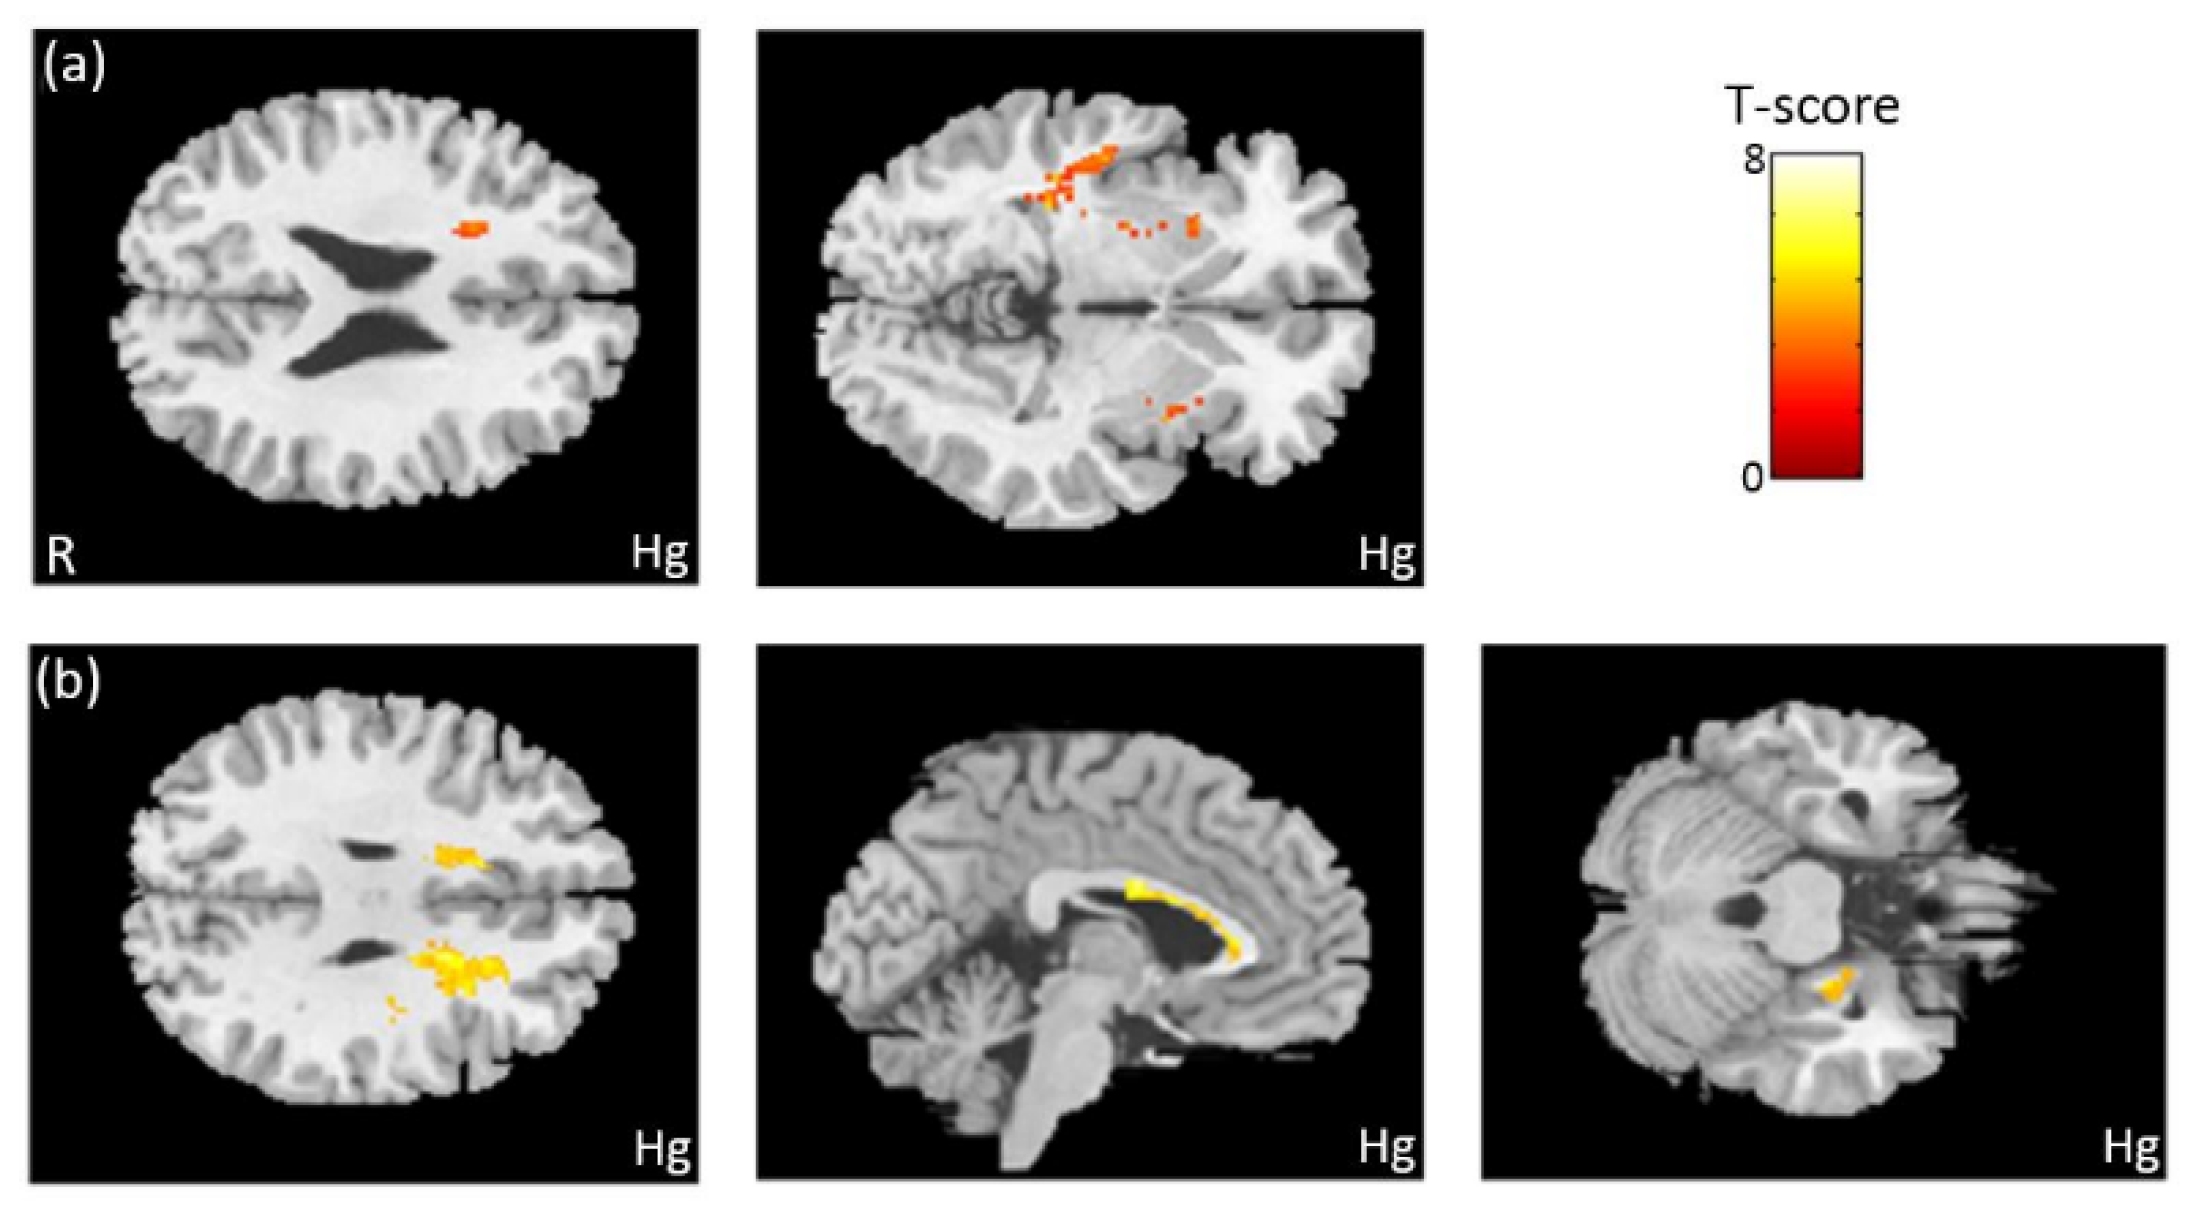

3.7. The Association Between Heavy Metals and GQI

4. Discussion

4.3. Brain Volume and White Matter Structure Associated with Heavy Metals